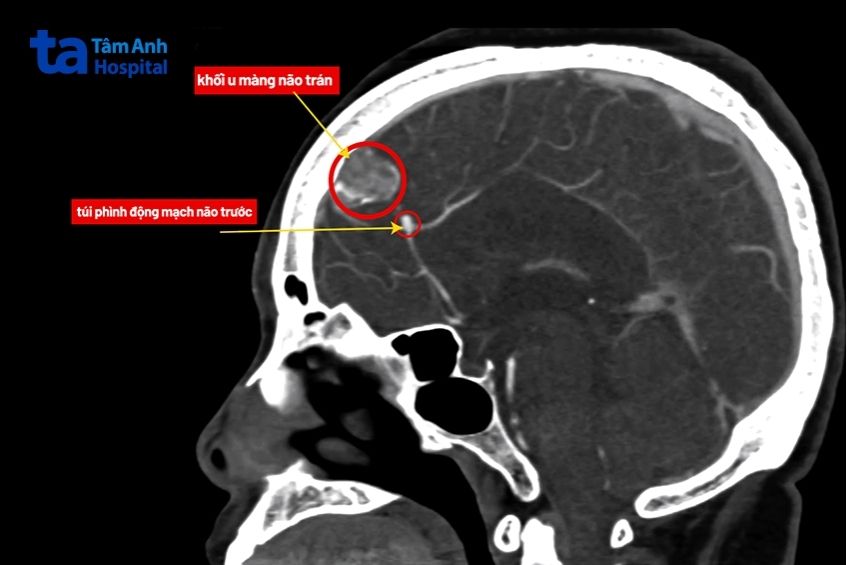

TS.BS Nguyễn Đức Anh, Trưởng khoa Ngoại Thần kinh Cột sống, Bệnh viện Đa khoa Tâm Anh Hà Nội thăm khám lâm sàng và chỉ định người bệnh chụp cộng hưởng từ và chụp mạch não. Kết quả phát hiện bà Hiền có túi phình động mạch não trước và một khối u màng não. Đây là hai bệnh lý có thể gây nguy hiểm trực tiếp đến tính mạng nếu không xử trí kịp thời. Túi phình có nguy cơ vỡ gây xuất huyết não. U màng não phát triển có thể chèn ép, tạo áp lực lên nhu mô não và hệ thần kinh.